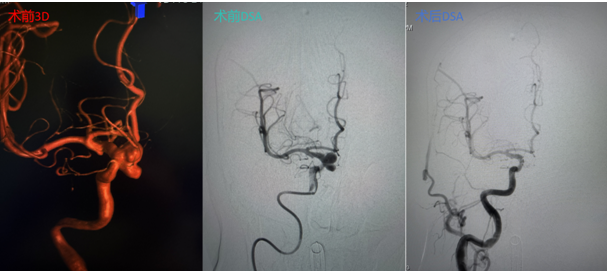

在与家属充分沟通并获得同意后,手术团队制定了周密的手术方案。手术中,专家凭借精湛的微导管超选技术在桡动脉建立通路,在复杂迂曲的血管中“翻山越岭”,精准抵达右侧颈内动脉,成功避免路经主动脉弓。面对宽颈动脉瘤的难题,团队巧妙运用支架辅助栓塞技术,将一根根弹簧圈严密填塞入动脉瘤囊内。

术后即刻造影显示,动脉瘤腔内血流消失,载瘤动脉通畅无阻,手术取得圆满成功,患者已康复出院。